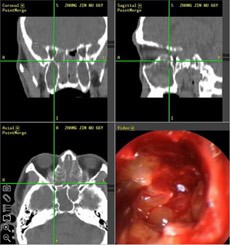

【典型案例】反复手术切息肉 复发导致嗅觉减退5年之久

张先生家住兰州,是典型的鼻窦炎患者,经常会出现鼻塞、流脓涕、头痛、等症状,去过多家医院,治疗结果并不理想,复发不说,到现在张先生的嗅觉已经严重减退,味道都快闻不出来了。

经推荐,跨省来到西安新城中大耳鼻喉医院耳鼻喉科治疗,入院后,经医生诊断并推荐使用“”,在鼻内窥镜的帮助下切除鼻息肉,术后经过10天后复诊并无复发现象。

(图为:鼻窦炎患者治疗现场) (图为:鼻窦炎治疗图谱)

[原理阐述]: “”技术以“CT片检查”和“ 狼牌鼻内窥镜”精准定位,借助“ 美敦力微创切割动力系统”和“ 杰西消融系统” , 精准扫净四对鼻窦炎症,避免“漏诊盲区”、迁延其它鼻窦复发;同时功能性鼻腔术后修复和绿色技术,轻松清除额窦、上颌窦、筛窦和蝶窦等合并症,迅速恢复鼻部功能,治疗恢复期比同等手术缩短三倍,被称为“多窦一清”高端技术。

优势1,精准定位: “ 功能性鼻内窥镜系统”自带的冷光源的亮度相当于无影灯20倍,清晰的视野使治疗达到更精细的效果,3.5mm的小孔可将病变组织放大数倍,并将同步拍摄到的影象传送到相应的的电脑屏幕上,患者病变部位可被医生一览无余,可告别过去盲目凭手感和经验操作的“盲人摸象”时代。